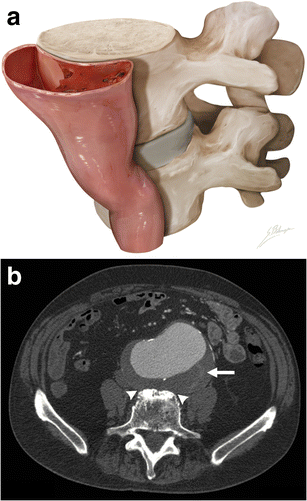

Draped aorta sign

Draped aorta sign. a Illustration depicts loss of normal aneurysm wall convexity. The posterior wall of the aorta moulds to the anterior surface of the vertebral body. b Axial enhanced CT of an 85-year-old man with abdominal pain. The posterior aortic wall follows the contour of the anterior portion of the vertebra, with loss of fat planes between the aneurysm and vertebra (white arrowheads). Discrete thrombus fissuration (white arrow) is also seen. These are both signs of impending AAA rupture